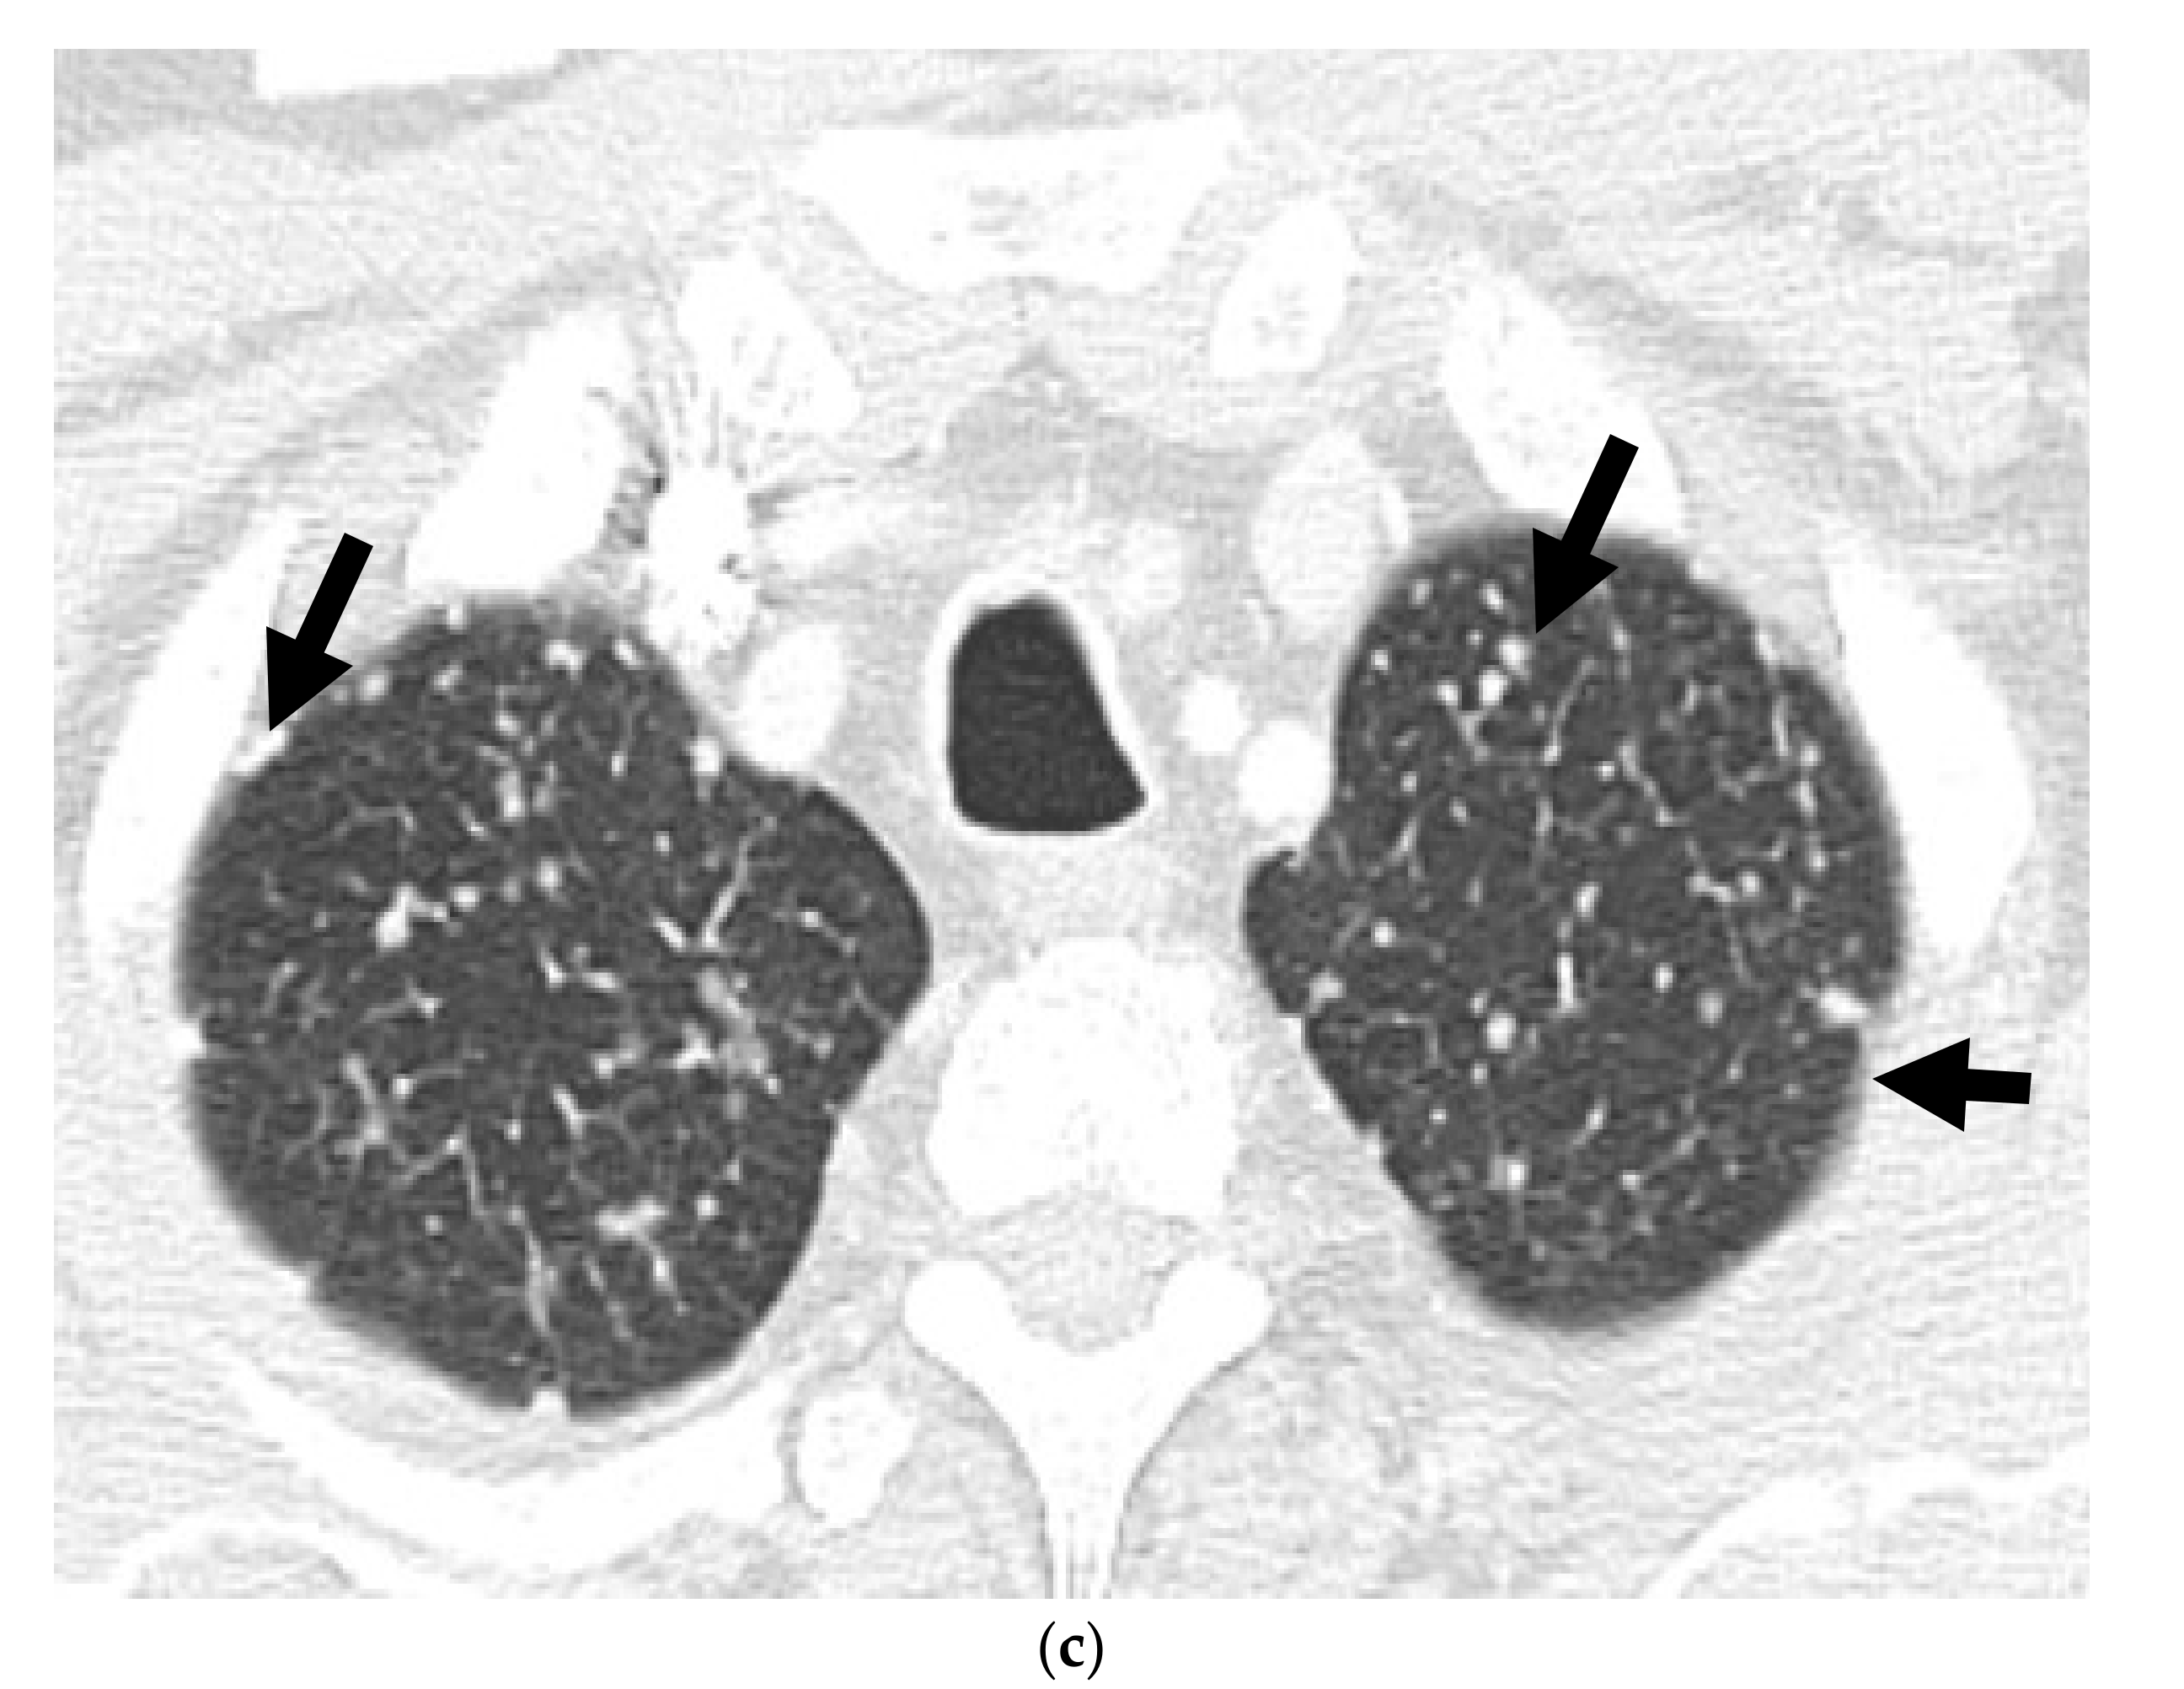

Figure 4.

A 56-year-old male with prior hormonal therapy for 2 years and external beam radiation therapy for the biopsy-proven diagnosis of prostatic adenocarcinoma in 2008. Follow-up MRI pelvis performed for recurrent elevated serum PSA 6 years after shows a left posterolateral peripheral zone prostatic nodule with restricted diffusion on ADC map (a) and avid early enhancement on the dynamic postcontrast T1W images (b), suspicious for recurrent prostatic neoplasm (arrow). This was biopsy proven to be prostatic adenocarcinoma. Further follow-up MRIs after 12 years showed rapidly enlarging left prostatic neoplasm (long arrow) with regional left internal iliac lymphadenopathy (short arrow) on ADC image (c) along with metastatic left common iliac and retroperitoneal lymphadenopathy. This was biopsy proven to be metastatic prostatic neuroendocrine carcinoma. Prostatic mass showed heterogeneous hypermetabolism on the axial color fused image of the Ga-68 DOTATATE PET-CT (d). The nodal metastases (arrow) were without suspicious hypermetabolism due to poorly differentiated neuroendocrine neoplasm/carcinoma component.

Molecular imaging in prostate cancer offers the advantage of improved sensitivity over conventional imaging. Multiple PET tracers are available for the evaluation of prostate carcinoma, particularly in the restaging setting. The FDA-approved radiotracers include 18F-FDG, 18F-NaF, 11C/18F-Choline, and 18F-Fluciclovine. 68Ga-DOTATATE PET (Figure 4 and Figure 5) has been found to be promising and is now being established for the evaluation of neuroendocrine neoplasms of the lungs, thyroid gland, and gastrointestinal tract. However, it is still not used for routine clinical use in patients with NEPC [43,44]. PSMA has received attention as a useful biomarker in the imaging of prostate cancer, particularly detecting disease at lower PSA levels. However, the expression may be reduced that can potentially lead to false negatives in highly evolved tumors with neuroendocrine features [45]. Another emerging PET tracer is an analog of bombesin or antagonist of the gastrin releasing peptide receptor. Bombesin-like peptides are also overexpressed in NEPC and are an area of active research [46].

2.3.2. 68 Gallium Labelled Somatostatin Analogs (68Ga-DOTATATE or 68Ga-DOTANOC)

68Ga-DOTATATE or 68Ga-DOTANOC, are 68Ga labeled somatostatin analogs that bind with high affinity to the somatostatin receptor 2 (SSTR2), which is highly expressed by NEPCs, enabling their identification by SSTR2 tracers [54,55]. 68Ga-DOTATATE or 68Ga-DOTANOC PET can be used to evaluate bony metastases and predict treatment response in these cases [54,56]. 68Ga-DOTATATE has a reported sensitivity and specificity of 82% and 90%, respectively, for detecting disease in cases of biochemically-relapsed prostate cancer [57]. This may be presumably useful in evaluation and management of low and intermediate grade neuroendocrine neoplasms, as shown in cases of gastroenteropancreatic neuroendocrine neoplasms [53,58,59]. At the same time, one should also remain aware of the false positive diagnosis in the setting of prostatitis due to inflammatory uptake [60,61] or in case of standard prostatic adenocarcinoma with inflammatory cell infiltrates [62]. Inflammatory tracer uptake usually gives rise to low- or very low-grade hypermetabolic activity and may be a clue in some of these cases [60].

There is no core difference in staging between prostatic adenocarcinoma and NEPCs. The TNM staging system, developed by the American Joint Committee on Cancer (AJCC), is the most commonly used staging method to assess the tumor status (T), lymph nodes (N), and metastasis (M) [70]. Unlike prostatic adenocarcinoma, clinical tumor stage 1 is uncommonly seen in cases with NEPC and they usually present with higher stages, with more visceral and nodal metastases with predominantly lytic bone lesions. Hence, NEPC is clinically suspected when a prostate cancer is seen with absent or a low/moderate rise in PSA, presents at advanced stage, or has a predominance of visceral and/or bone metastatic disease (Figure 2). In addition, NEPC is also suspected when the prostate cancer becomes unresponsive to ADT with rapid disease worsening (Figure 3 and Figure 4) [68,69]. Paraneoplastic syndrome is also a potential distinguishing feature for NEPCs, especially SCNC, with Cushing’s syndrome being the most common manifestation [71,72]. Currently, the reference standard for the diagnosis of NEPCs is pathologic examination showing the above microscopic features, plus the presence of neuroendocrine IHC markers, e.g., NSE, SYN, and CgA [16,73].